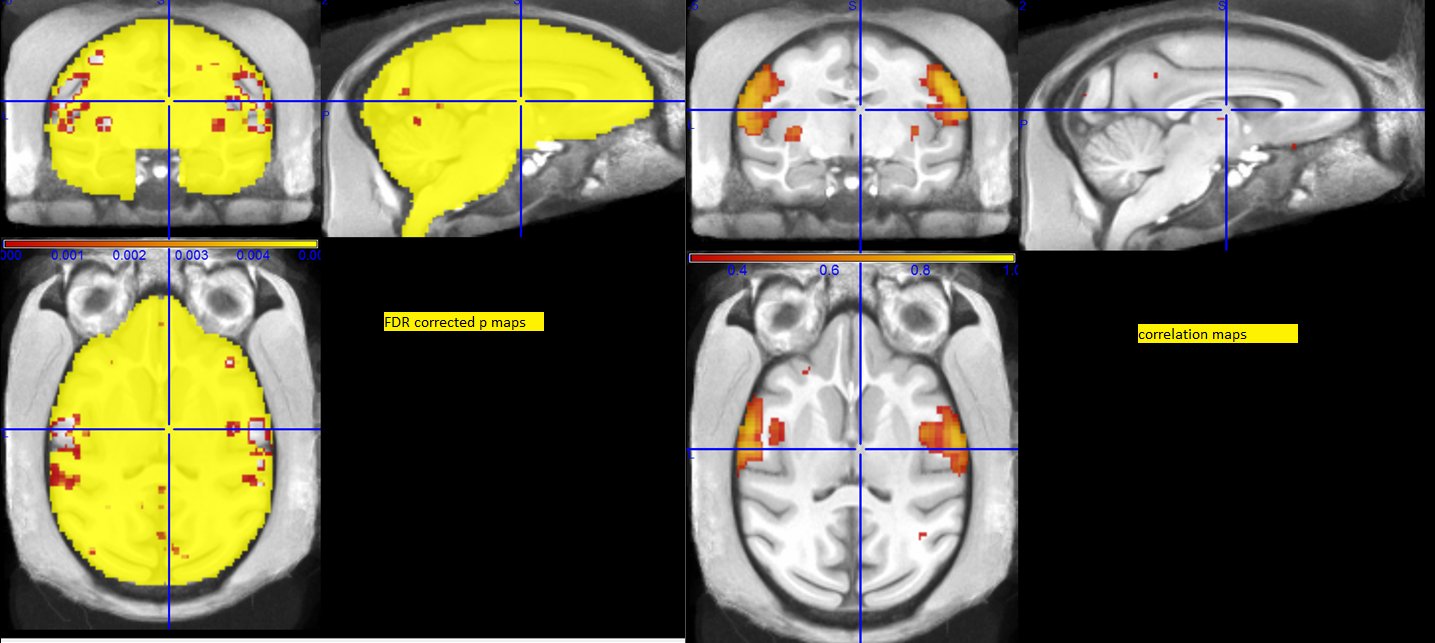

I am little bothered by how my FDR corrected map looks after my analysis. Mine is a single subject resting state analysis with 4 sessions per analysis. I am attaching the the FDR corrected map (p_FDR<0.005) and corresponding correlation coefficient map (r>0.3). I am visualizing it in MRiCRon. It looks like the FDR correlation map is showing the boundary region of the correlated areas. Is there a better way to visualize it?